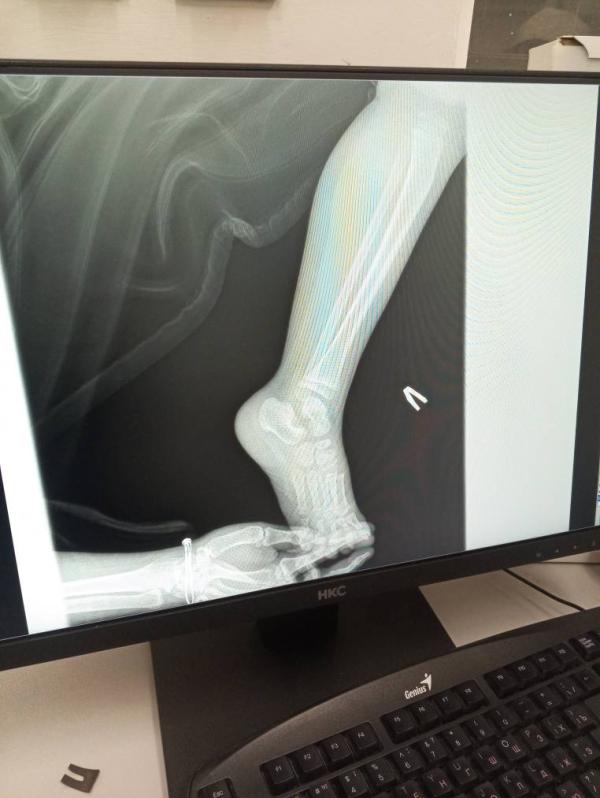

Снимок вчера сделали , перелом яц аьл отправили домой, но и цу те да ц хут, йа куьг ц 1утит, просто йоьлх са кхачин са цо, ху дир дар те((